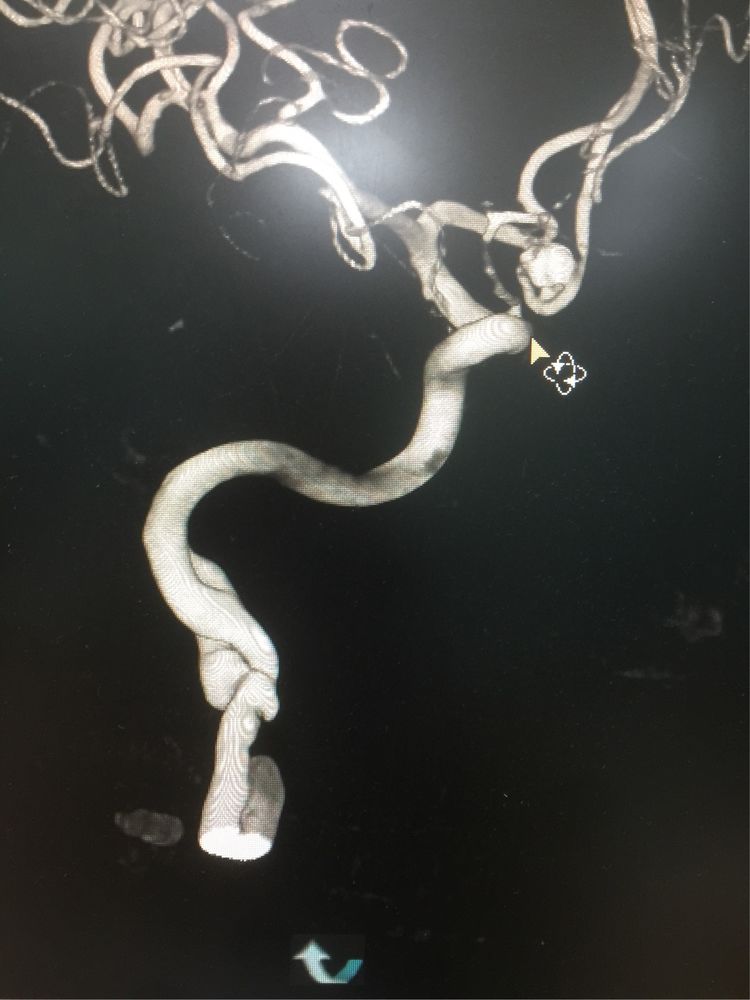

夹层动脉瘤假道及破口如图示。

3D重建,下方夹层破口及部分夹层动脉瘤未显示。